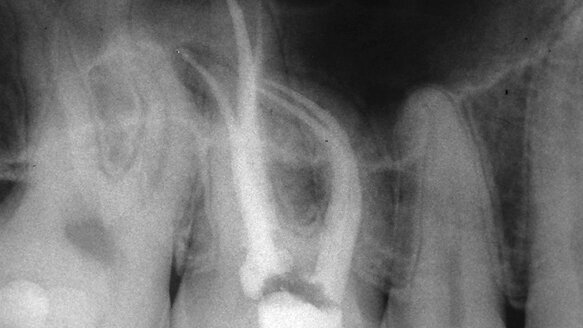

Figures 5–7 show a maxillary molar that was prepared apically to a minimum of 35, 1 mm back to a 40 and the implementation of the single NiTi instrument we use in reciprocation, the 25/06 to blend in the middle and apical thirds. The dimensions of the preparation were in accordance with the research that recommended a 35 for effective irrigation.

From the outset, using the thinnest 06 reamers, all the walls of the canals were shaped by the reamers’ vertically oriented blades. If we are serious about removing the tissue in the thin isthmus extensions that often exist, we must address them at the very beginning of instrumentation when instruments are the thinnest.

With the ability to be pre-bent and limited to a short arc of motion, the stainless-steel reamers both unrelieved and relieved can adapt to any situation that may be encountered. The result is not only one that looks good in the mesio-distal plane, but is cleansed three dimensionally to a degree that assures cleaner canals and superior obturation while leaving the walls of the canal defect free.